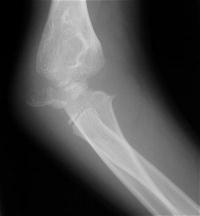

Five years later, he has limited motion (E/F 35/100) and painful clicking with elbow flexion and extension.

Plain films show humeral osteophytes and posttraumatic changes of the capitellum and radial head.